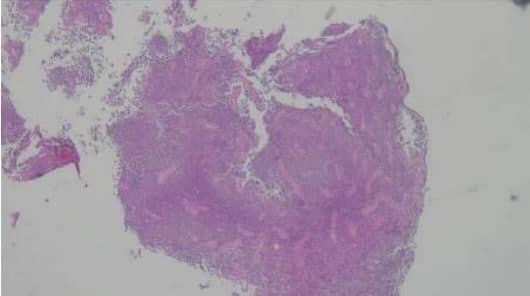

病理切片診斷結果為貓淋巴瘤,可惜後續小花二次貧血且伴隨急性腎衰竭,最後主人決定帶回家安寧。